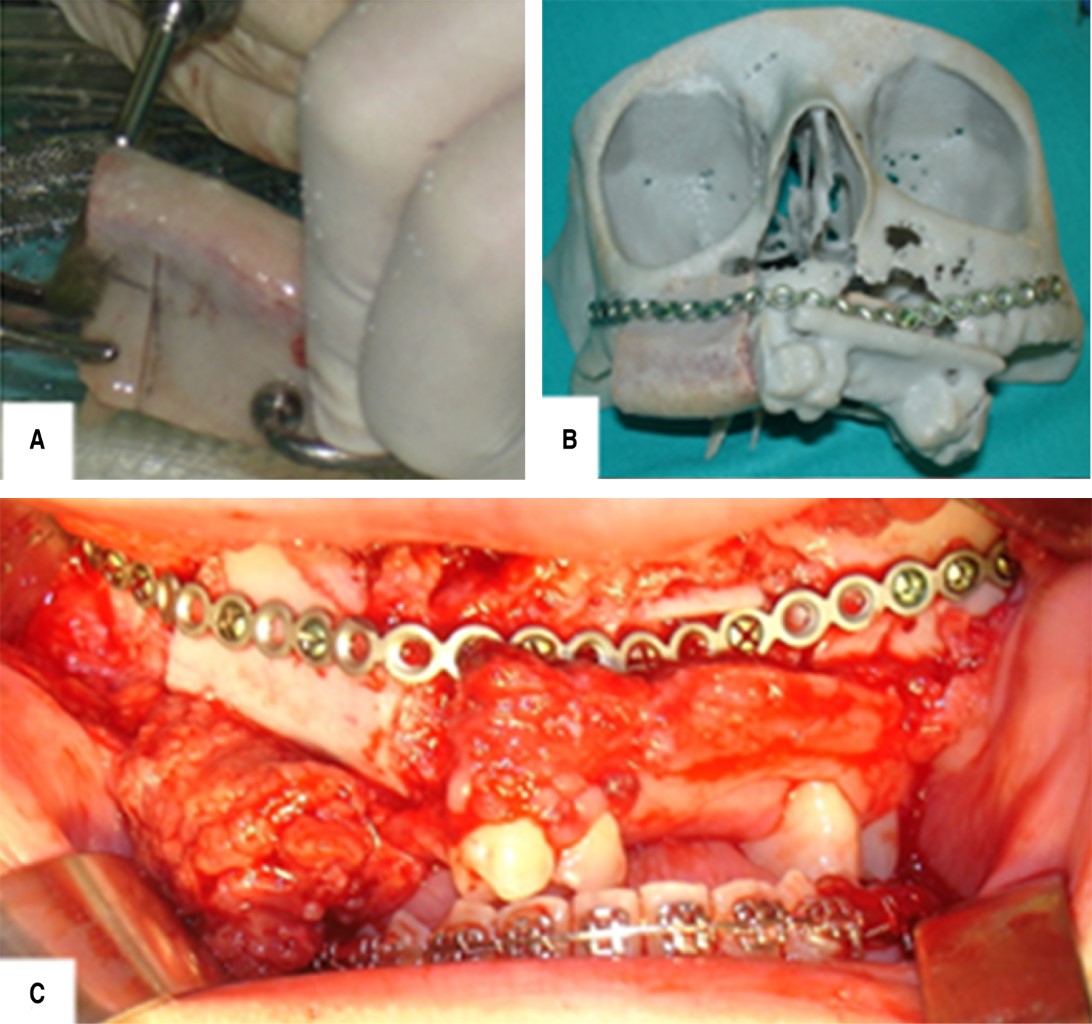

Juvenile trabecular ossifying fibroma maxillary with sarcomatization: 18-years follow-up

Ossifying fibroma a benign neoplasm of fibro-osseous tissue, with well-defined limits histologically characterized a large amount of fibrocellular and mineralized tissue. This pathology is classified two categories, including juvenile trabecular ossifying fibroma (TrOF) and psammomatoid (PsOF). Although the characteristics of these lesions are presented in a similar way, the great difference between them is the average age of presentation: 6-11.5 years the trabecular and from 12-18.9 years older the psammomatoid. Between these two groups there are histological variants and among them is the possible and unusual presentation of malignancy within the histology. The aim of this report is to describe the treatment of an eight-year-old female patient with a diagnosis of highly aggressive juvenile ossifying fibroma with points of possible sarcomatous transformation in maxillary without recurrences clinical, radiographic and tomographic follow-up for 18 years.